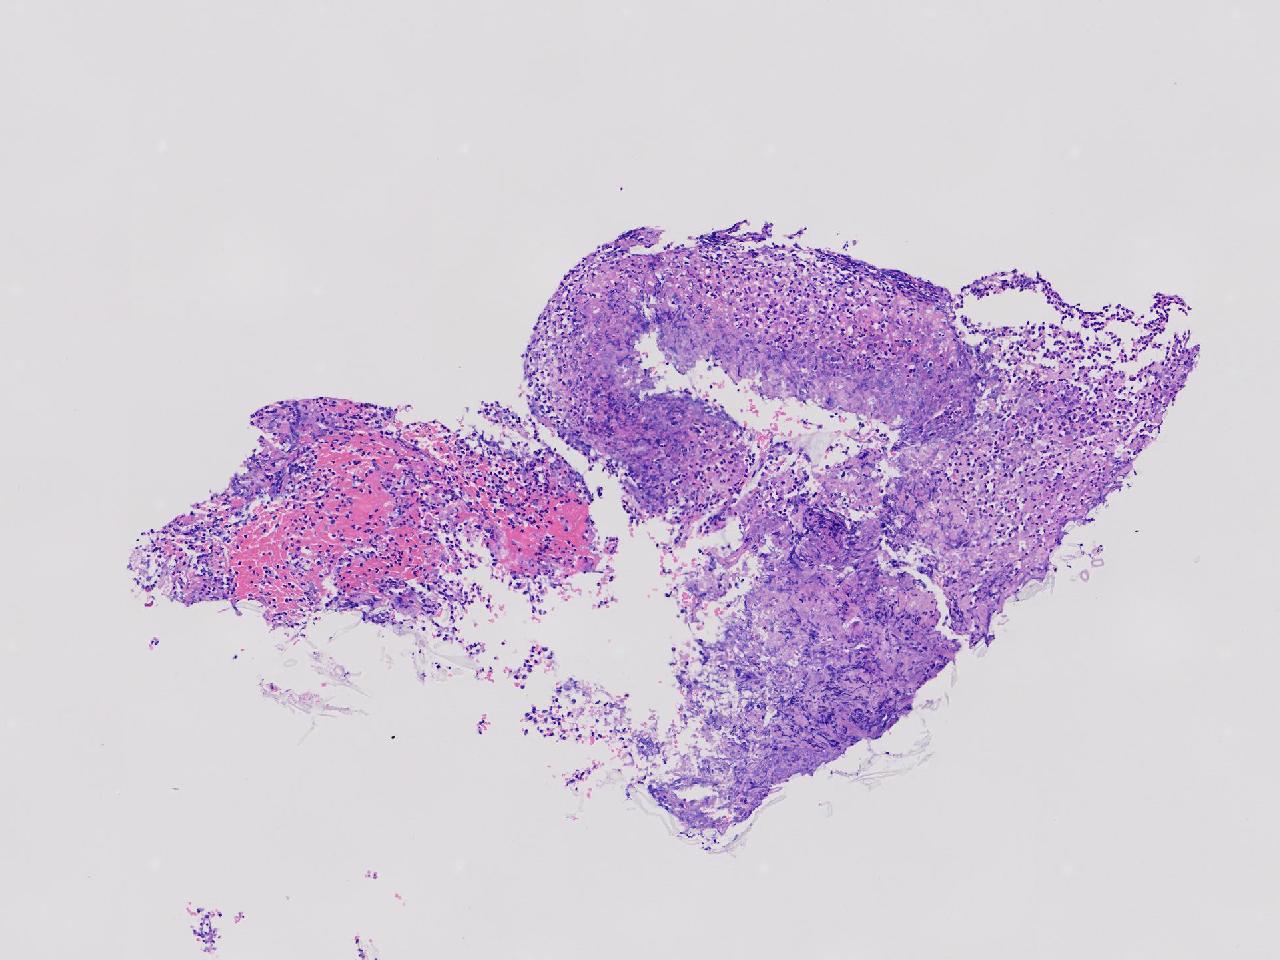

炎? 低瘤变?

胃体上部见一大小约2厘米的溃疡灶,表覆白苔,周边充血,水肿明显,活检3块。

胃体活检

灰白色不整形软组织3块,直径均0.2厘米。

深在性囊性胃炎,少量溃疡组织

深在性囊性胃炎伴溃疡